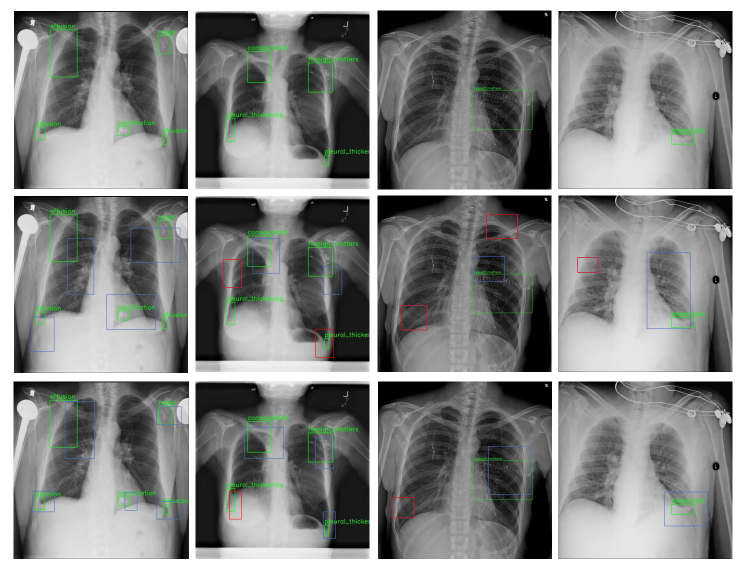

Results of disease detection in 4 CXRs are visualized in Fig. 7. From top to down are original images, results of the original ‘Faster R-CNN C4’, and results of the variant of ‘Faster R-CNN C4’ which is improved by our module. The green, blue and red boxes stand for ground-truths, true positives and false positives, respectively. The experimental results demonstrate that the contralateral context information extracted by our proposed module is beneficial to the detection of diseases in CXRs.